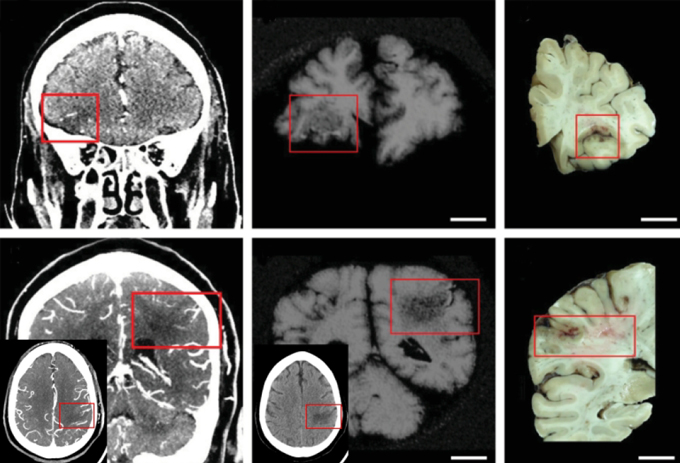

That absence suggests that the virus is affecting the brain in other ways, possibly involving blood vessels. So Nath and his team scanned blood vessels in post-mortem brains of people who had been infected with the virus with an MRI machine so powerful that it’s not approved for clinical use in living people. “We were able to look at the blood vessels in a way that nobody could,” he says.

Damage abounded, the team reported February 4 in the New England Journal of Medicine. Small clots sat in blood vessels. The walls of some vessels were unusually thick and inflamed. And blood was leaking out of the vessels into the surrounding brain tissue. “You can see all three things happening at the same time,” Nath says.

Those results suggest that clots, inflamed linings and leaks in the barriers that normally keep blood and other harmful substances out of the brain may all contribute to COVID-related brain damage.